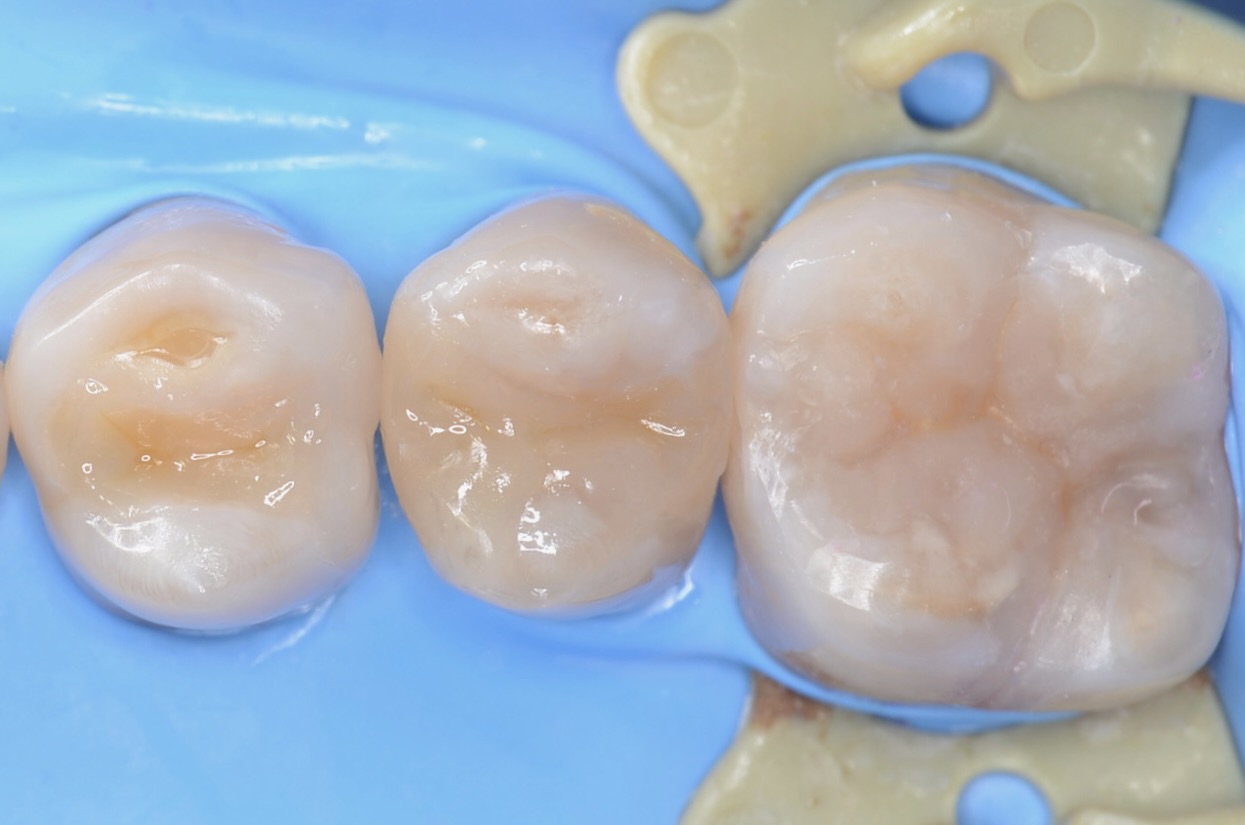

6番ダイレクトボンディング

5番ダイレクトボンディング

日を変えて治療になります。 -

4番ダイレクトボンディング

-